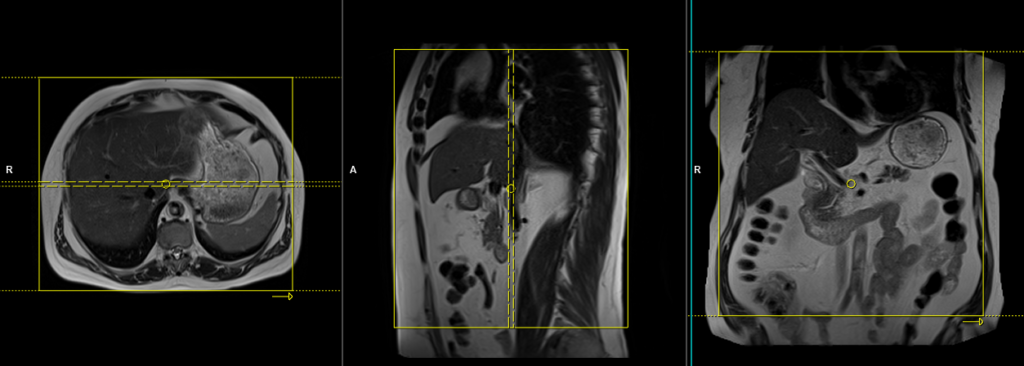

localiser Free-breathing

To localize and plan the sequences, it is essential to acquire a three-plane T2 HASTE localizer initially. These fast single-shot localizers have an acquisition time of under 25 seconds and are highly effective in accurately localizing abdominal structures.

T2 tse BLADE(PROPELLER) axial respiratory gated

Plan the axial slices on the coronal free-breathing localizer images and position the block horizontally across the liver, as shown. Verify the positioning in the other two planes. Establish an appropriate angle in the sagittal plane, aligning it horizontally across the liver. The slices must be sufficient to cover the entire liver from the diaphragm down to the C loop of the duodenum. The phase direction can either be right to left or anterior-posterior, as radial k-space sampling will eliminate potential motion artifacts. Use phase oversampling to prevent radial k-space-related artifacts.